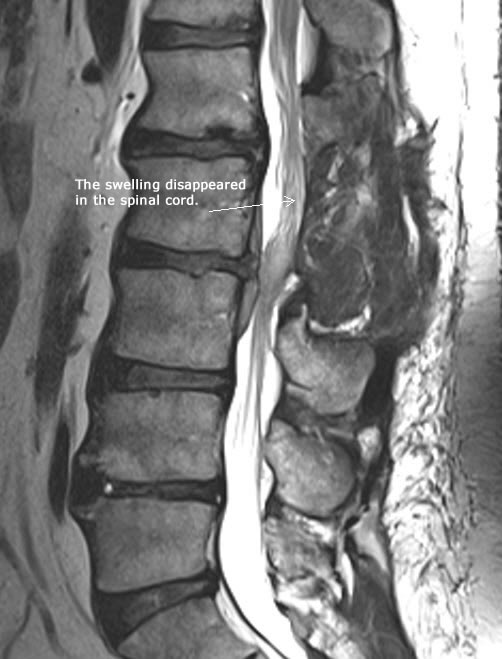

Fig-2. MRI done 06-10-2025 showing the disappearance of the swelling above the surgical lesion and the severely compressing extrusion disappeared with adhesions in the surgical area.